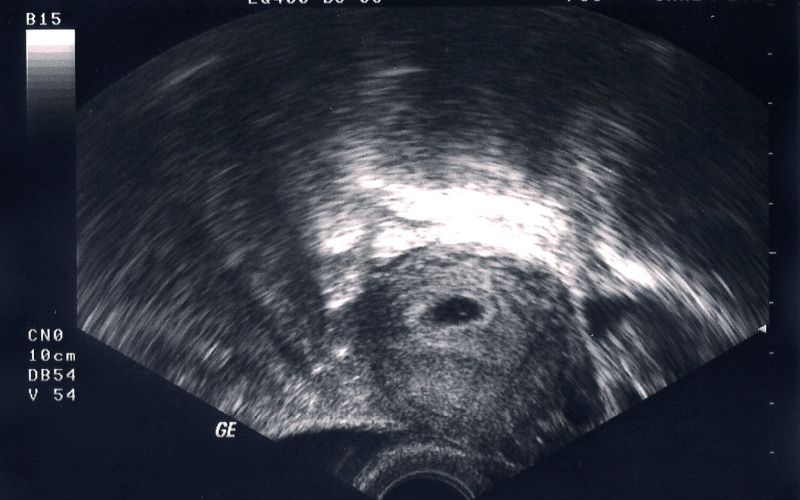

Thai 4 – 5 tuần tuổi

Đây là giai đoạn thai còn nhỏ, chỉ mới là phôi thai nên việc hút thai cũng đơn giản hơn. Phương pháp thường được áp dụng ở tuổi thai này là hút điều hòa kinh nguyệt. Cách này sử dụng ống hút thai nhỏ, bơm hút chân không bằng tay để hút sạch túi thai ra ngoài.

Thai 6 - 12 tuần tuổi

Từ khi thai được 6 - 12 tuần tuổi thường sẽ sử dụng thủ thuật hút thai chân không. Cách này cần phải sử dụng cả thuốc gây tê và máy hút chân không để can thiệp qua cổ tử cung đưa phôi thai ra ngoài. Quá trình hút thai chân không được thực hiện trong khoảng thời gian từ 15 - 20 phút.